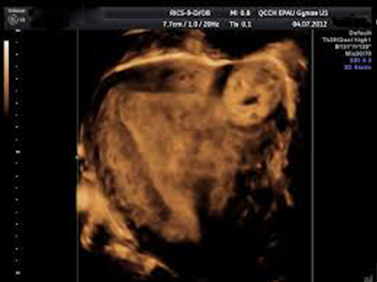

• Surface mode: Για την απεικόνιση τοιχωματικών ανωμαλιών (πολύποδες ενδομητρίου, υπενδομήτρια άλως, μορφώματα ωοθηκών και μαστών).

Η διαδικασία της λεπτομερειακής μελέτης του σώματος της μήτρας, των ωοθηκών και του μαστού, χρησιμοποιεί ηχητικά στοιχεία για να καθορίσει περιοχές που θεωρούνται τμήμα μιας συγκεκριμένης δομής. Έτσι αναγνωρίζονται μορφολογικά χαρακτηριστικά της παθολογίας για παράδειγμα η παρουσία υγρού εντός της ενδομητρικής κοιλότητας, παρουσία ηχογενών δομών που προβάλουν μέσα στην ενδομητρική κοιλότητα ή συμπαγούς βλάβης που καταλαμβάνει την ενδομητρική κοιλότητα, η τις ωοθήκες η τούς μαστούς και ελέγχεται πληρέστερα η εξωτερική επιφάνεια και η παρυφή των νεοπλασμάτων και οριοθετείται η σχέση τους με παρακείμενους ιστούς και όργανα.